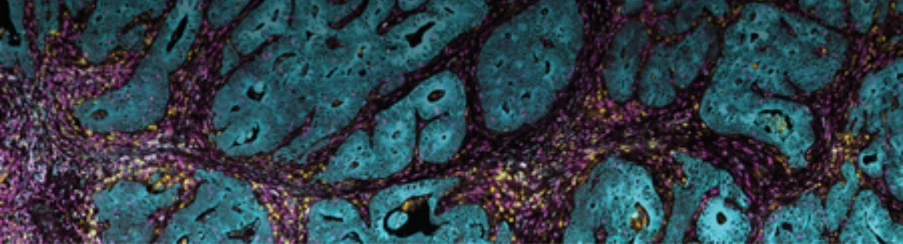

Advanced Pathology Services for Fast, Reliable Data: Histopathology, IHC, IF, and In Situ Hybridization with Automated Precision

H&E and IHC staining

Map of ovarian cancer tumor microarray

Tissue microarrays are paraffin blocks containing cores from multiple tumor samples, allowing high-throughput analysis for biomarker screening and pathology research.

Researchers use TMAs to validate biomarkers, evaluate drug targets, and stratify patient populations by analyzing expression patterns across tumor cohorts.

Explore the complete transcriptome and over 570 protein targets individually or in tandem, utilizing a range of sample inputs including whole tissue sections, tissue microarrays (TMAs), or organoids.